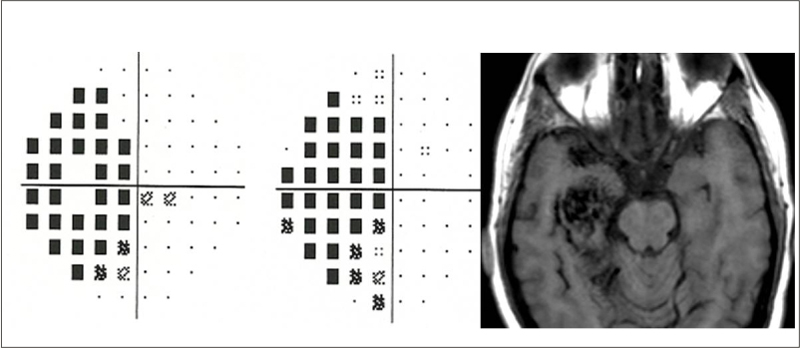

- Papiledema

El papiledema, por definición, es el edema de papila producido por el aumento de presión intracraneal (PIC). La RM craneal es la prueba de elección para su estudio causal, pero el carácter urgente de esta patología hace que habitualmente sea una TC craneal el primer paso en el protocolo diagnóstico. La TC tiene más utilidad en el caso de que se aprecien hemorragias en el fondo de ojo, pues permite identificar rápidamente un sangrado intracraneal agudo (Figura 2).

Figura 2. Borramiento papilar con múltiples hemorragias retinianas adyacentes (izquierda) y hemorrragia subaracnoidea en TC (derecha)